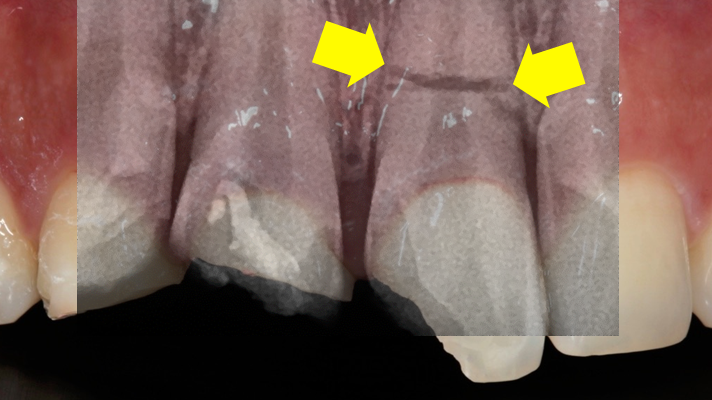

Clinical case: Extraction, immediate placement & loading using

R2GATE solution in aesthetic zone

- Courtesy of Dr. Jong-Cheol Kim, Korea-

Dr. Jong Cheol Kim, immediate loading, digital guided surgery, Digital ONE-DAY Implant, maxillary anterior, #21, guided surgery, immediate loading, AnyRidge, R2GATE, Mega ISQ, MEG Torq, R2GATE Full Surgical Kit